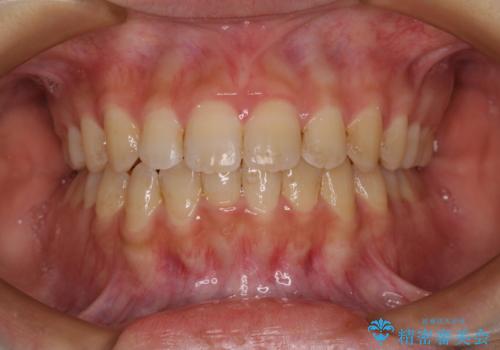

- 大学病院にて装置を装着したものの、治療が十分に受けることができないとのことで転院をされた患者様です。

上顎歯列が前方にあり、口元が閉じにくくなっていたため、既に装着されている装置を使用して上顎歯列全体を後方に移動させていくこととしました。

舌の突出癖があり、それが原因で上下前歯に隙間ができていたため、改善のためのトレーニングを行うように指示をしました。

舌の突出癖の影響か、なかなかスペースが閉じきらず、治療期間は予定よりも長期間となりました。

舌突出癖改善のトレーニングの重要性を認識することとなりました。